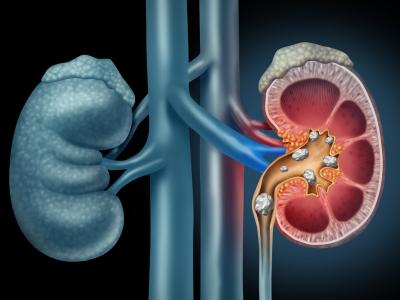

आंवला में ऐसे तत्व होते हैं जो पथरी के इलाज में सहयक हैं। पथरी की समस्या में आंवला कारगर उपाय साबित हुआ है। पथरी होने पर कुछ दिनों तक आंवले का सूखा पाउडर खाने से आपको समस्या से राहत मिल सकती है।